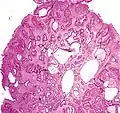

| Hyperplastic polyp | Colorectal (unless otherwise specified) | Serrated unbranched crypts | if polyps are more than 100 | ![]() |

Serrated polyposis syndrome |

| Juvenile Polyp | Upper GI tract and colon | Cystically dilated glands with expanded lamina propria | Not inherently, may develop dysplasia | ![]() |

Juvenile polyposis syndrome, identical polyps in Cronkhite–Canada syndrome |